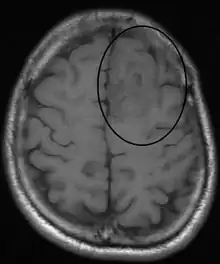

Oligodendroglioma arise mainly in the frontal lobe and in 50–80% of cases, the first symptom is the onset of seizure activity, without having any symptoms beforehand.[2] Headaches combined with increased intracranial pressure are also a common symptom of oligodendroglioma. Depending on the location of the tumor, many different neurological and neuropsychological deficits can be induced, including, but not limited to, visual loss, motor weakness, cognitive decline, and anxiety.[3] A computed tomography (CT) or magnetic resonance imaging (MRI) scan is necessary to characterize tumor size, location, and hetero- or homogeneity. Final diagnosis relies on biopsy and histopathologic examination of the tumor mass.[2]